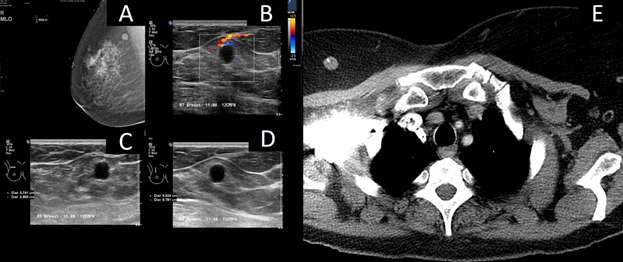

Biopsy proven breast metastasis from retroperitoneal leiomyosarcoma with additional metastasis to the liver and lungs:

References: